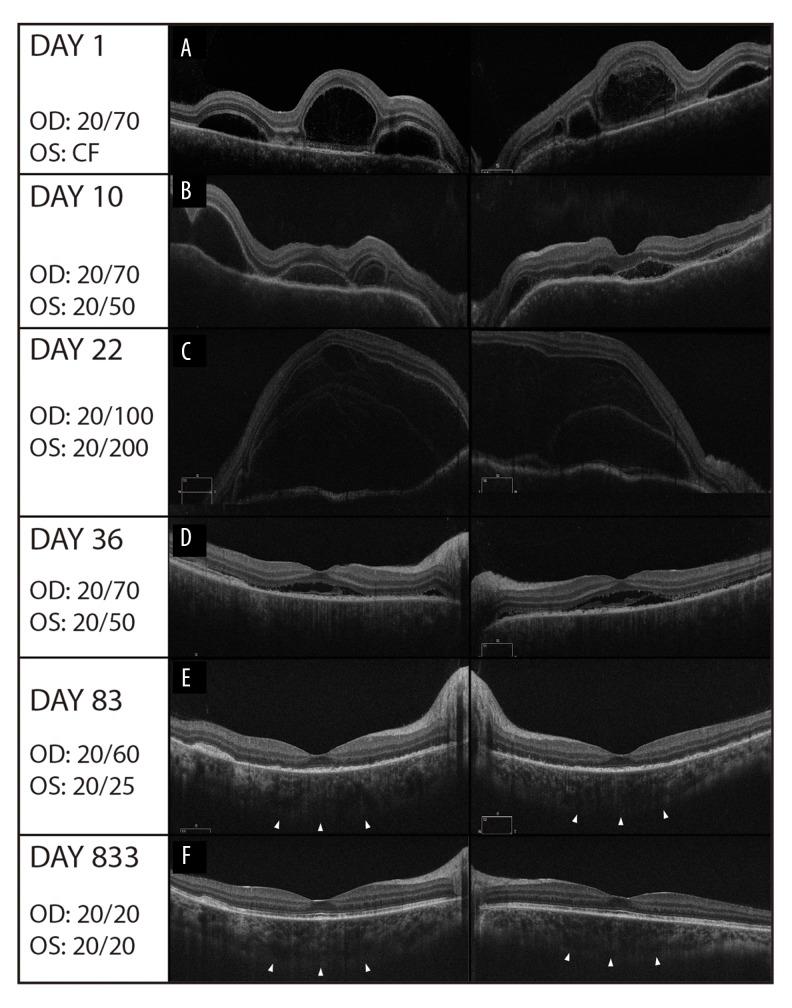

BACKGROUND The aim of this study was to describe the case of a 27-year-old woman who developed Vogt-Koyanagi-Harada (VKH) disease in the 13th week of pregnancy, who was treated with high-dose oral corticosteroids and azathioprine due to its persistent course. CASE REPORT A 27-year-old East Indian woman in her 13th week of pregnancy presented with bilateral decreased visual acuity and metamorphopsia due to bilateral serous retinal detachments and was diagnosed with Vogt-Koyanagi-Harada (VKH) disease. Multimodal imaging, including blue light fundus autofluorescence (FAF), structural spectral domain optical coherence tomography (SD-OCT), en-face OCT, and OCT angiography (OCT-A), was performed at presentation and follow-up, being particularly helpful for identifying recurrences. Her treatment consisted of high-dose corticosteroid therapy, and azathioprine had to be added as an adjuvant due to the aggressive behavior of the disease. She gave birth to a healthy baby at 31 weeks of gestation and remained with 20/20 vision at 8 weeks postpartum. CONCLUSIONS To the best of our knowledge, this is the first report on the use of azathioprine in VKH disease during pregnancy with a successful outcome. Multimodal imaging avoiding the use of fundus fluorescein angiography is key in the diagnosis and follow-up of VKH disease in pregnant women.

背景 本研究的目的是描述一名27岁女性的病例,该女性在妊娠第13周患上原田小柳-原田病(VKH病),因其病情持续,接受了高剂量口服糖皮质激素和硫唑嘌呤治疗。病例报告 一名27岁处于妊娠第13周的东印度女性,因双侧浆液性视网膜脱离出现双侧视力下降和视物变形,被诊断为原田小柳-原田病(VKH病)。在初诊和随访时进行了多模态成像,包括蓝光眼底自发荧光(FAF)、结构频域光学相干断层扫描(SD-OCT)、表面OCT和OCT血管造影(OCT-A),这对识别复发特别有帮助。她的治疗包括高剂量糖皮质激素治疗,由于病情进展,不得不加用硫唑嘌呤作为辅助治疗。她在妊娠31周时产下一名健康婴儿,产后8周视力仍保持在20/20。结论 据我们所知,这是第一例关于在妊娠期间使用硫唑嘌呤治疗VKH病并取得成功结果的报告。避免使用眼底荧光血管造影的多模态成像对于孕妇VKH病的诊断和随访至关重要。